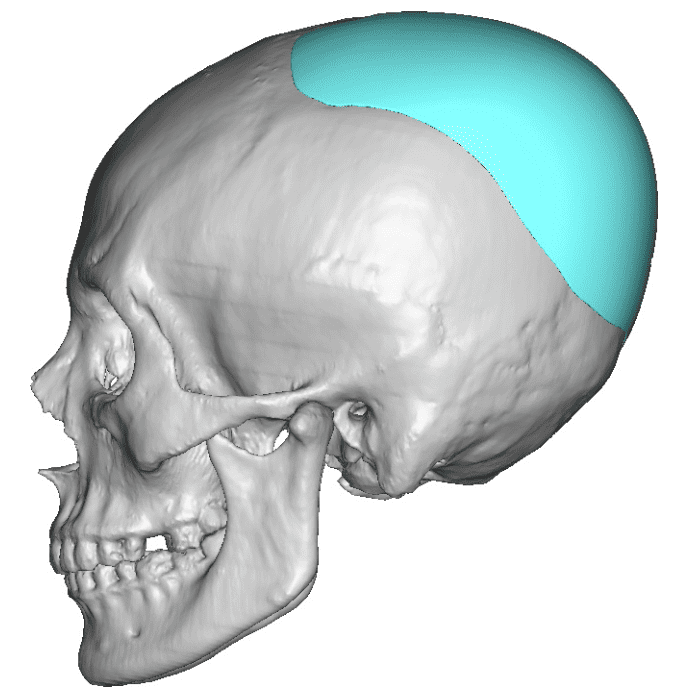

Desire for an improved head shape so that it looks rounder and not so peaked or sloped.

Placement of custom skull implant for parasagittal augmentation to create a rounder head shape. An example of what appears to be a high sagittal crest that is really low parasagittal skull areas.

Desire for an improved head shape so that it looks rounder and not so peaked or sloped.

Placement of custom skull implant for parasagittal augmentation to create a rounder head shape. An example of what appears to be a high sagittal crest that is really low parasagittal skull areas.